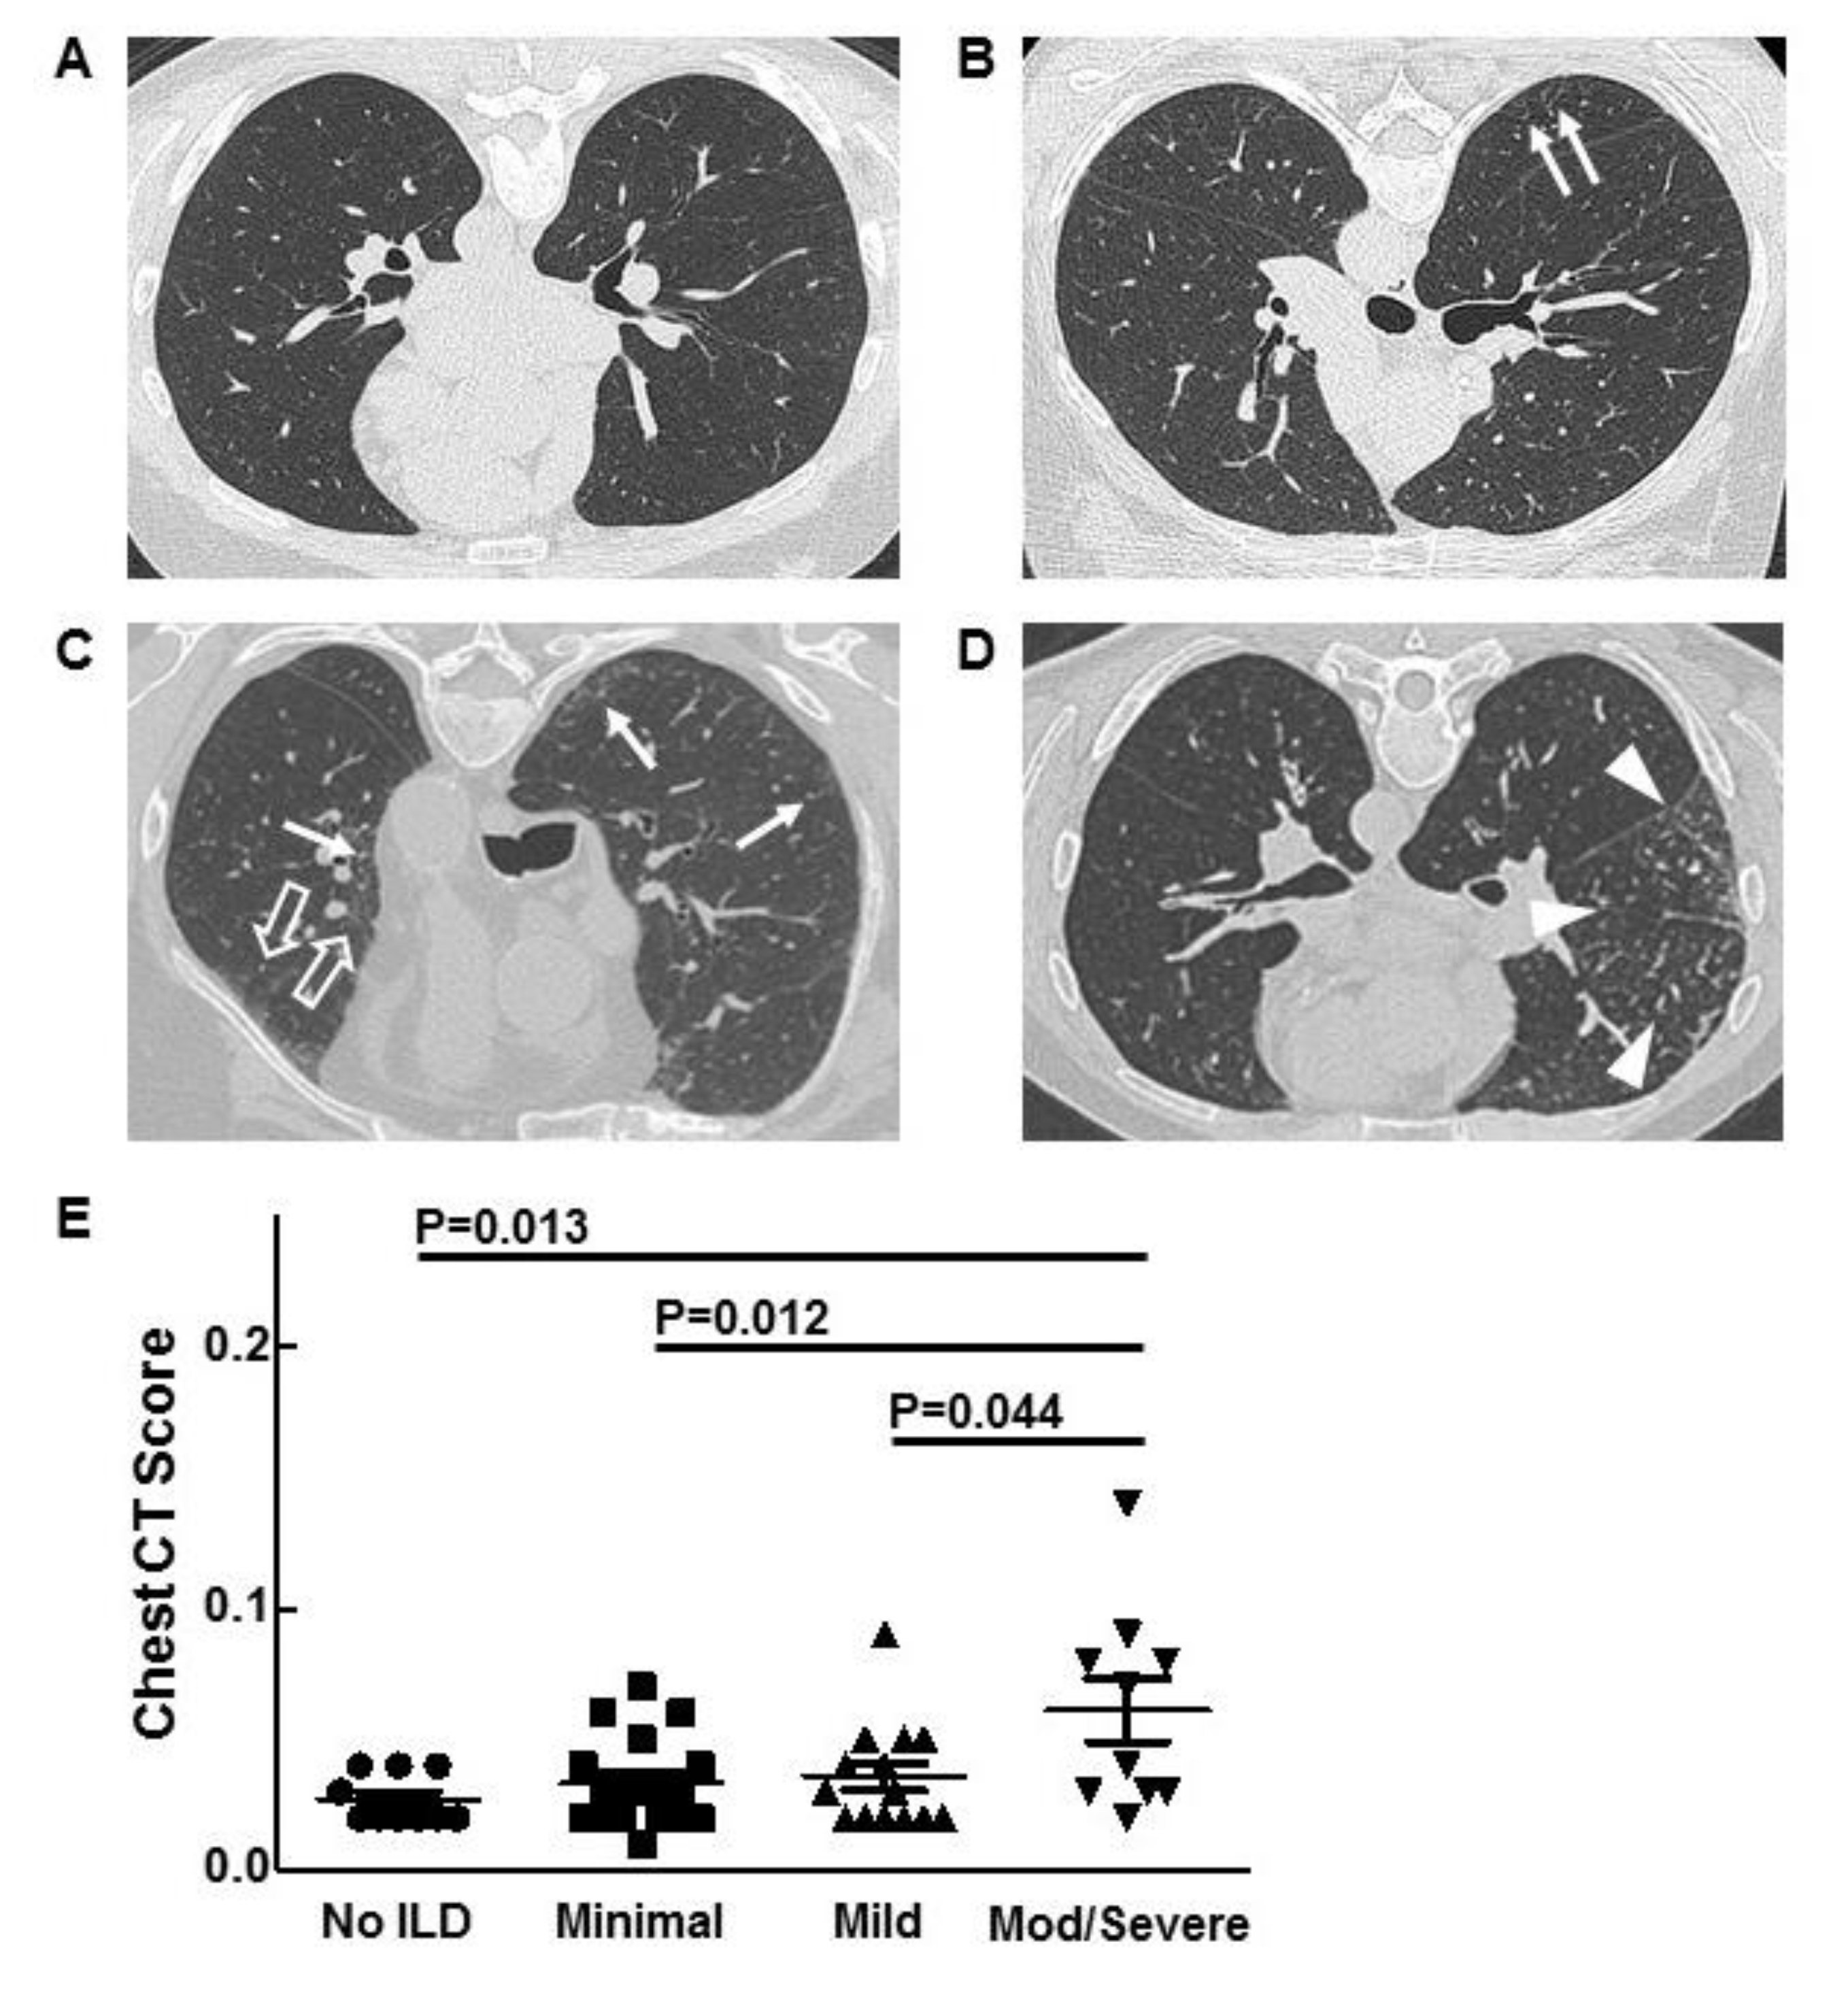

Sixty-two patients (45 males, 17 females) with ECD were evaluated for ILD. ECD affected at least one extrapulmonary site in all patients. Based on chest CT findings, 12 (19.5%) had no ILD, 20 (32%) had minimal ILD, 18 (29%) had mild ILD, and 12 (19.5%) had moderate/severe ILD (Figure 1A–D, Table 1). One patient with minimal ILD had a prior pneumonectomy to resect a tumor, which was interpreted as a paraganglioma. Mean ages were 51.8, 49.2, 55.5, and 55.8 years, respectively, for ECD patients without ILD, minimal ILD, mild ILD, and moderate/severe ILD.

Figure 1.

Representative high-resolution chest-computed tomography scan images from patients with Erdheim–Chester disease (ECD) and no interstitial lung disease (ILD) (A), minimal ILD with subpleural reticulations (arrows) (B), mild ILD with reticular ground-glass opacification (open arrow) (C), and moderate (mod) ILD with reticular nodular opacity (arrow heads) (D), are shown. Chest-computed tomography scan scores for patients with ECD and varying severity of ILD are displayed (E).

HRCT scans were analyzed by a previously validated automated quantification computer program [18]. The scores for ECD patients with moderate/severe ILD were significantly higher than those of patients with no ILD, minimal ILD, and mild ILD (p = 0.013, p = 0.012, and p = 0.044, respectively) (Figure 1E). HRCT scan scores did not correlate with lung function.